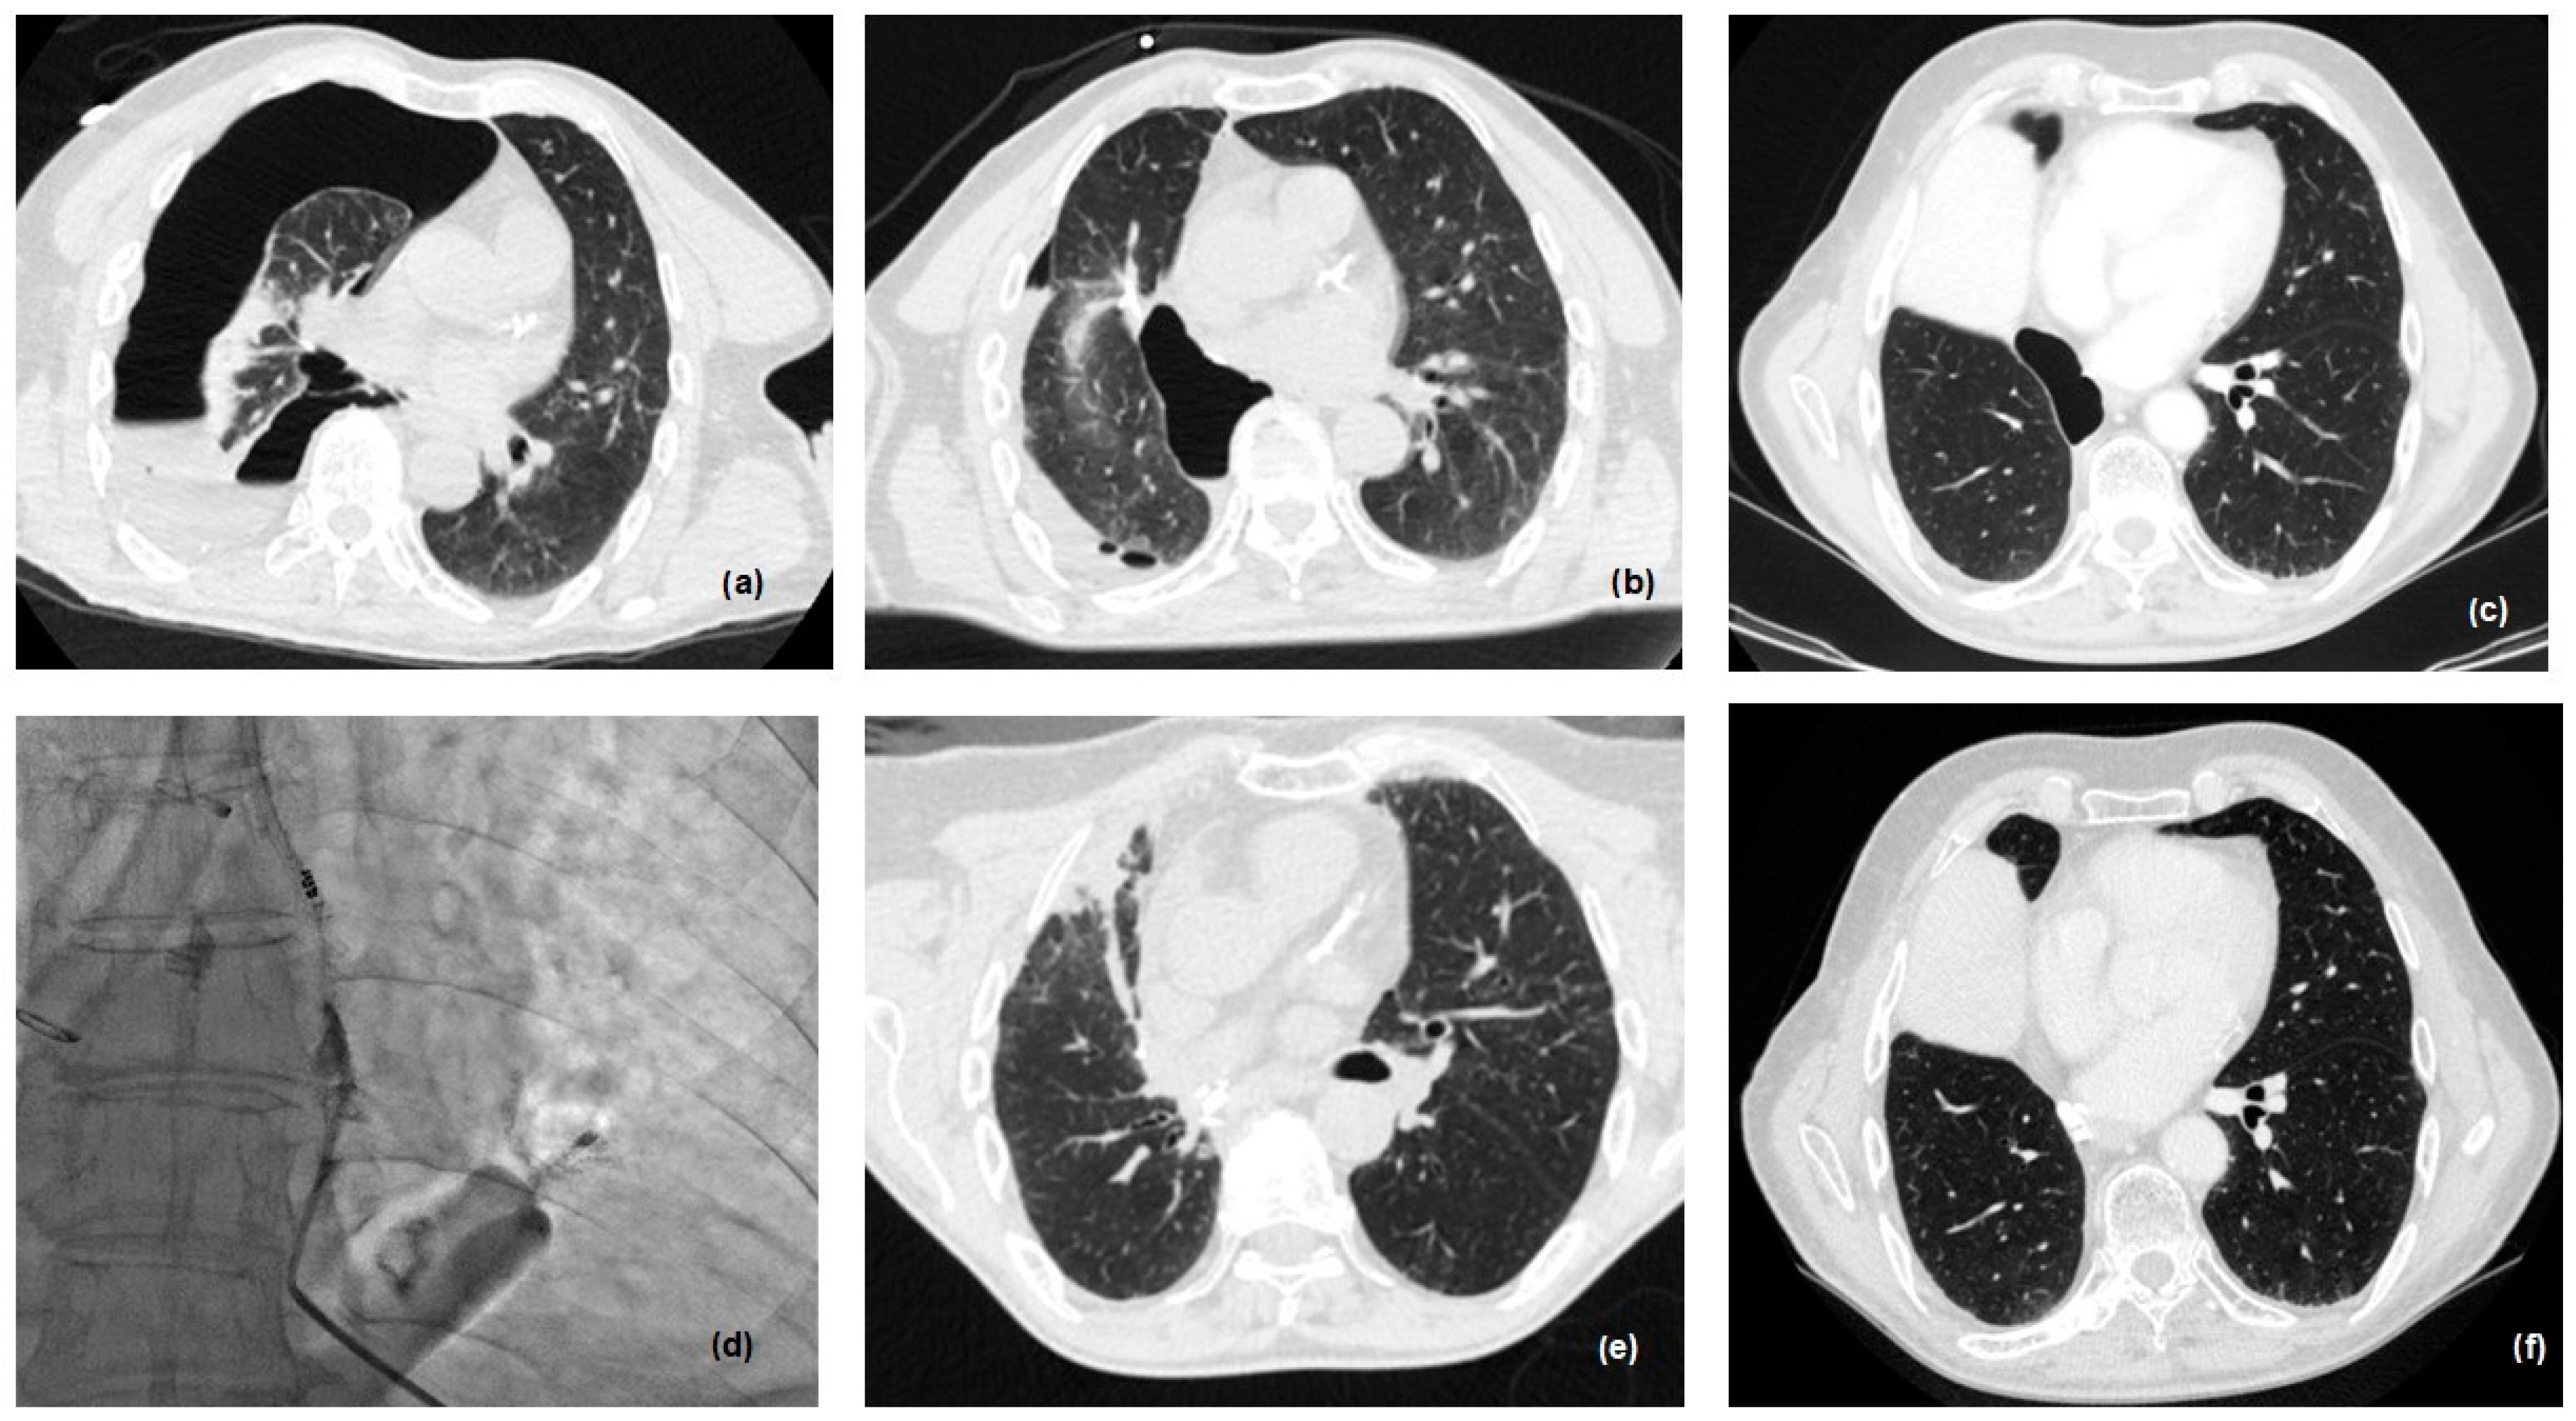

2.3. New Therapeutic Horizons: Percutaneous Treatment of Small and Late BPF

| 41 | F | 57 | Lower bilob. | 47 | 6 | Percutaneous injection of glue | No | No | Alive (18 months) |

| 44 | M | 70 | Lower bilob. | 12 | 5 | Percutaneous injection of glue | No | No | Alive (7 months) |